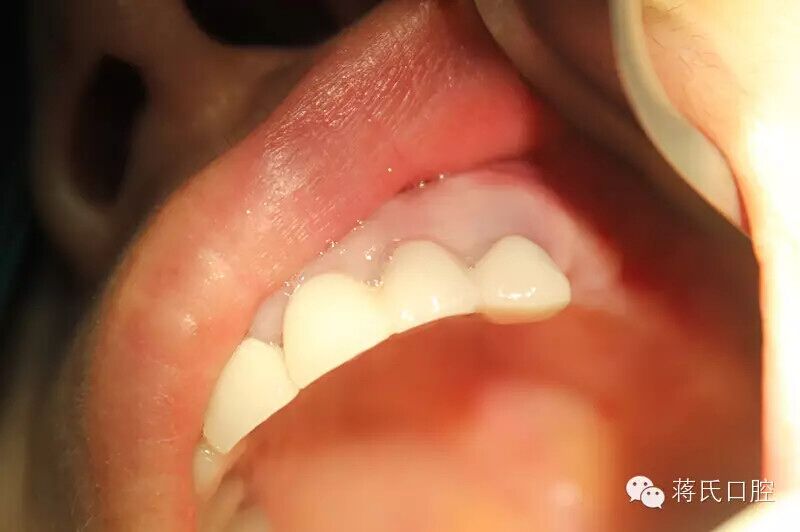

17.修復(fù)完成的冠

18.修復(fù)完成后口內(nèi)